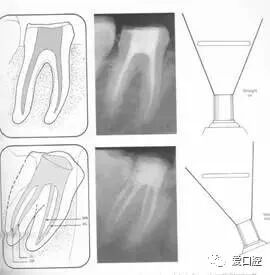

便宜形态是自切端或咬颌面朝向根尖的直线开扩尖锥形态,减少污染物推出根尖孔,方便冲洗、根管充填和侧壁施压。

保持形态是根尖狭窄部内 1 — 2mm 的一段距离,由扩大器回转切割而不贴根管壁提拉切割制成,是扩大器的原始形态(近似平行)。在测试主牙胶尖时给测试者有一个牵引抵抗 (tugback) 的感觉。

抵抗形态是根管预备的根尖形态,它是由扩大器或根管锉尖端 75 度角自然切割而成。其目的是防止根管充填材超出根尖孔,并且使根尖封闭更加严密。

( 1 )直线通路:根管治疗时需要一个直线通路,直线通路能够达到根尖三分之一

测量标准:以允许根管器械直线并直接进入根尖 1/3 且不接触冠方各壁为标准。